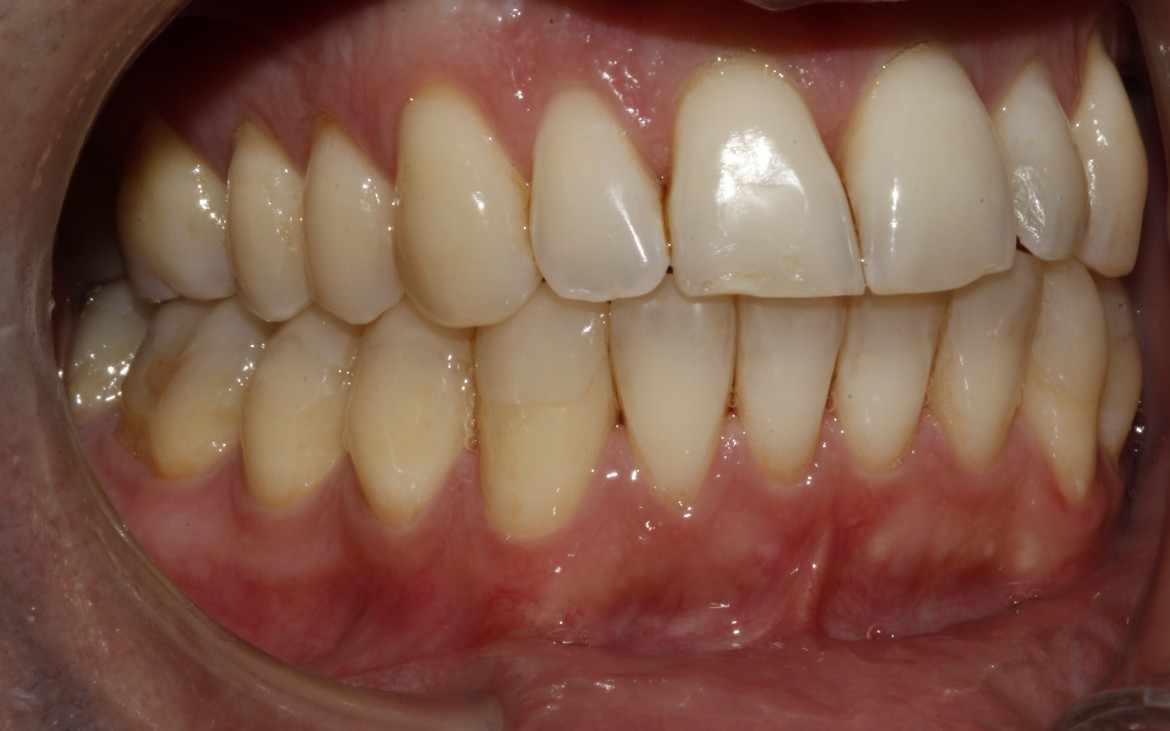

Paciente Sr. G. M. , sexo masculino, 28 anos de idade . Oclusão CL II de Angle com Overjet de 6mm e apresentando atresia das arcadas superior e inferior.

1 – Oclusão tipo classe II de angle com overjet acentuado de 6mm.

Maxila em posição centralizada em relação a base do crânio, mandibula retruida.

(vista lateral lado direito).

2- Oclusão classe ii de angle.

Ausência de guia anterior e guia lateral exercida em demasia pelos 1° pré-molares.

(vista lateral esquerda.)